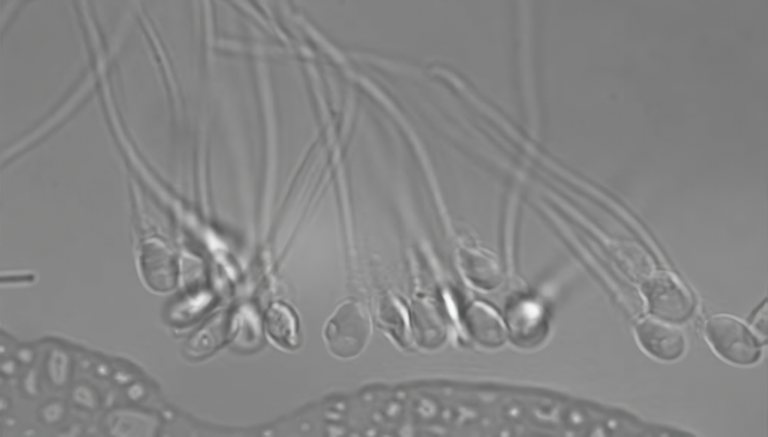

Les hommes exposés à des insecticides ont moins de spermatozoïdes

Les hommes les plus exposés aux insecticides présentent une concentration inférieure de spermatozoïdes. C'est la conclusion qui ressort de l'examen de 25 études réalisées dans le monde au cours des 50 dernières années. Cette étude a été publiée dans le magazine Environmental Health Perspectives.

En particulier, l’influence de deux types d’insecticides les plus couramment utilisés a été étudiée: les organophosphates et les carbamates de N-méthyle. Et ils ont clairement constaté qu'il existe un lien direct entre l'exposition à ces insecticides et la faible concentration de spermatozoïdes.